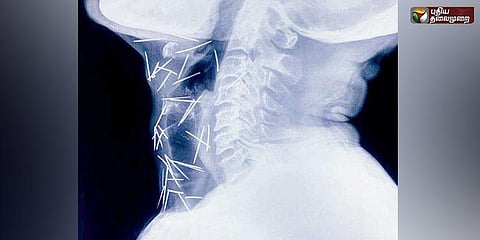

தொண்டைக்குள் 150 குண்டூசிகள் - அதிசய மனிதருக்கு ஆப்ரேஷன்

வடஇந்தியாவைச் சேர்ந்த முதியவர் ஒருவரின் தொண்டை மற்றும் உடல் உறுப்புகளில் இருந்த குண்டூசி குவியல்களை நீண்ட நாள் போராட்டத்திற்கு பின் மருத்துவர்கள்

அகற்றினர்.

உத்தரபிரதேச மாநிலத்தைச் சேர்ந்தவர் பத்ரிலால் மீனா. இவர் கடந்த சில ஆண்டுகளாக மூட்டு வலி மற்றும் சக்கரை நோயால் அவதிப்பட்டு வந்தார். இந்நிலையில்,

திடீரென அவருக்கு தொண்டை பகுதியில் வலி அதிகரித்து பேசமுடியாமல் போனதால் மருத்துவமனையில் அவரை அனுமதித்த மருத்துவர்கள் அவரின் தொண்டைப்

பகுதியில் எக்ஸ்ரே எடுத்து பார்த்தனர். அதில் அவரின் தொண்டை பகுதி முழுவதும் குண்டூசி குவியல்கள் இருப்பது கண்டுபிடிக்கப்பட்டது. இதனைக்கண்டு

அதிர்ச்சியடைந்த மருத்துவர்கள் அவரின் உடல் முழுவதும் எக்ஸ்ரே எடுத்தனர். அதிர்ச்சிக்கு மேல் அதிர்ச்சியாக அவர் உடலின் பல பகுதிகளில் குண்டூசிகள் இருப்பதை

கண்டு செய்வதறியாமல் மருத்துவர்கள் திகைத்தனர். இதனை சீர்செய்ய முடியாமல் 6க்கும் மேற்பட்ட மருத்துவமனைகள் கைவிரித்த நிலையில், கடைசியாக ஃபரிதாபாத் பகுதியில் உள்ள ஏய்ம்ஸ் மருத்துவமனையைச் சேர்ந்த மருத்துவர்கள் நீண்ட நாள் போராட்டத்திற்கு பின் அவர் உடலில் இருந்த 90 குண்டூசிகளை அகற்றினர். 150 குண்டூசிகள் அவர் உடல் முழுவதும் உள்ள நிலையில், தொண்டை பகுதியிலிருந்த 90 குண்டூசிகள் மட்டும் நீக்கப்பட்டுள்ளதால் நீண்ட நாளாக பேசமுடியாமல் தவித்து வந்த பத்ரிலால் மீனா தற்போது பேச ஆரம்பித்துள்ளதாக மருத்துவர்கள் தெரிவித்துள்ளனர். குண்டூசிகள் அவரின் உடலுக்குள் எப்படி சென்றது என்று தெரியவில்லை என பத்ரிலால் கூறிய நிலையில், அவரின் மனநிலை பரிசோதனை செய்ய மருத்துவர்கள் முடிவெடுத்துள்ளனர். மனஉளைச்சல் மற்றும் பல பிரச்சனைகளில் சிக்கியுள்ளவர்கள் இவ்வாறான செயல்களில் ஈடுபடுவது வழக்கம் என்றும் மருத்துவர்கள் தெரிவித்துள்ளனர்.